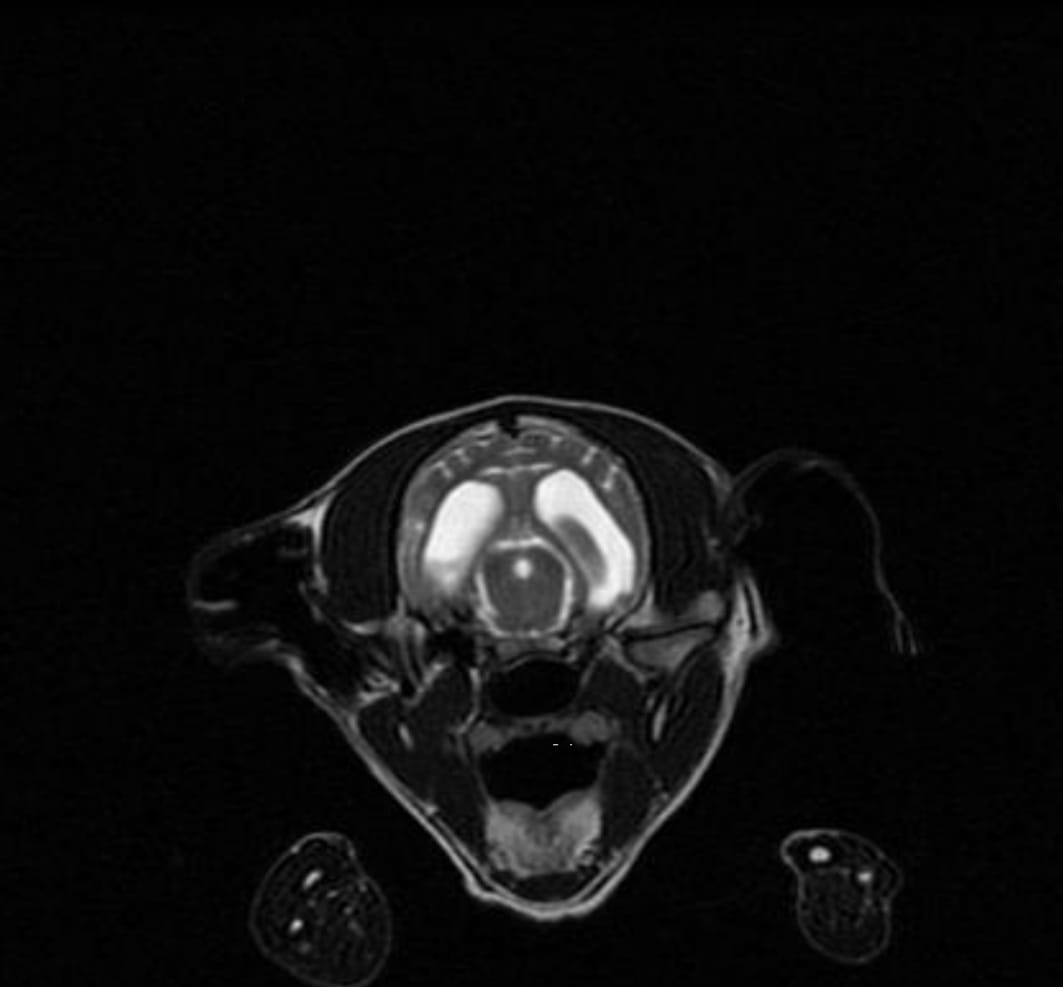

Der Klinikbericht zu der kleinen blinden Hündin ist da:

VETERINARY CLINIC Thessaloniki

„REPORT" Der Hund namens Nike wurde am 21/09/2022 mit neurologischen Symptomen vorgestellt: Ataxie, Desorientierung, Muskelzittern und unsicherer Gang. Nach der neurologischen Untersuchung wurde eine Erkrankung des Vorderhirns vermutet. Die Blutuntersuchung war innerhalb normaler Grenzen. Die Liquor-Analyse ergab keinen Hinweis auf eine Infektionskrankheit oder eine auf Steroide ansprechende Meningoenzephalitis. Es wird ein MRT des Gehirns und eine neurologische Untersuchung durch einen Facharzt für Neurologie empfohlen, um eine angeborene Hirnerkrankung zu bestätigen und die Prognose zu bestätigen. Die Untersuchungen von Nike sind beigefügt (s.Bilder)“

Diese Untersuchung (MRT) würden wir gern machen lassen, denn Nike hat ein Recht zu leben. Nur so können wir sie optimal fördern. Wir suchen also Paten, die mit uns für die kleine Kämpferin sorgen wollen. Bitte helft Nike!!!